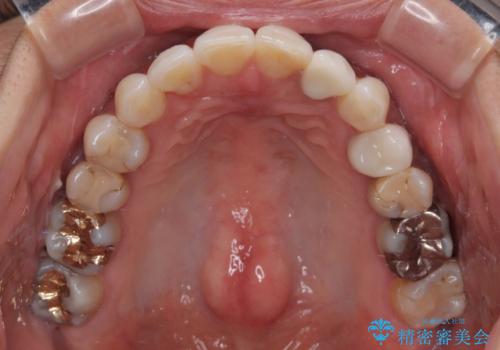

むし歯治療は、症状のある歯を矯正治療前に処置し、概ね歯列が整ったところで残りのは全て処置し、最後にインビザラインで歯列を仕上げることで、無駄なく治療を進めて行くこととしました。

しっかりと装着時間を守ってくださり、来院のタイミングに合わせてインビザラインの装着期間を調整するなど、協力いただいたおかけで、1年半の期間で全てを終えることができました。